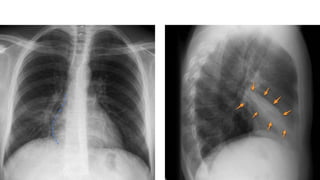

The right heartborder is blurred

Note the wedgeshaped opacity on the lateral CXR. The horizontal fissure (arrow) is depressed